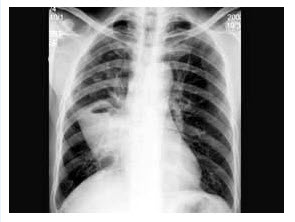

25、单项选择题

男,52岁,从事矿井工作32年,近几年出现气喘,呼吸困难,胸片如图,其最可能的诊断为()